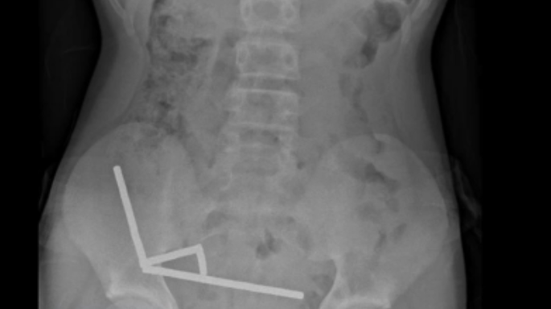

Exames revelaram que os ímãs haviam se agrupado em quatro correntes na parte inferior direita do abdômen, unindo diferentes seções do intestino com sua força magnética, segundo o relatório, que observou que algumas imagens foram distorcidas pelos ímãs. Os médicos então procederam com uma cirurgia exploratória.

Durante o procedimento, os cirurgiões descobriram que as correntes de ímãs estavam causando necrose por pressão – morte do tecido por pressão prolongada – em partes do intestino delgado e grosso. Eles conseguiram remover os ímãs, mas o menino precisou ter parte do intestino removido. Ele passou oito dias se recuperando no hospital antes de receber alta, informou o relatório.